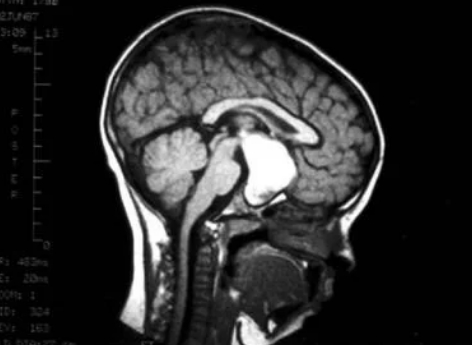

小金(化名)6歲時,開始間斷性的出現(xiàn)無力、厭食情況,跟小朋友們一起玩的時候也無精打采。家長以為是孩子有情緒,或是挑食習(xí)慣所致,就沒當(dāng)回事。隨著時間過去,小金的無力癥狀加重,惡心嘔吐、進食不佳、狀態(tài)低迷,出現(xiàn)嗜睡、左眼無光感等癥狀,到醫(yī)院經(jīng)過頭部CT檢查后才發(fā)現(xiàn),小金患上了小兒顱咽管瘤。

小兒顱咽管瘤是一種少見的中樞神經(jīng)系統(tǒng)(CNS)良性腫瘤,被認(rèn)為是由Rathke氏囊的殘余物引起的,靠近垂體。顱咽管瘤在兒童中常見,占兒童鞍區(qū)腫瘤的54%,鞍上區(qū)是大腦中蝶鞍上方的區(qū)域,而蝶鞍是腦下垂體所在的頭骨部分。所以,隨著腫瘤的擴大,正常的垂體組織會被壓縮并受損,導(dǎo)致部分或全部垂體激素的分泌逐漸喪失。這一腫瘤往往會導(dǎo)致失明、生長發(fā)育遲滯、甚至死亡的后果,常被人稱為“長在惡性區(qū)域的良性瘤”。

顱咽管瘤

手術(shù)切除是顱咽管瘤的主要治療手段,但顱咽管瘤常給神經(jīng)外科醫(yī)生帶來較大的挑戰(zhàn),因為顱咽管瘤的不同位置和侵及周圍神經(jīng)結(jié)構(gòu)(即下丘腦、垂體和視神經(jīng))的程度使大體全切除(GTR)變得困難,從而導(dǎo)致較高的復(fù)發(fā)率[2]。即使在完全切除后,這些病變?nèi)杂袕?fù)發(fā)的傾向,但當(dāng)切除次全時,復(fù)發(fā)率明顯增加。想要一個較高的切除率,并且能同時保護周圍神經(jīng)組織不受損傷,一個經(jīng)驗豐富、手術(shù)技術(shù)高超的神經(jīng)外科醫(yī)生是較為重要的。